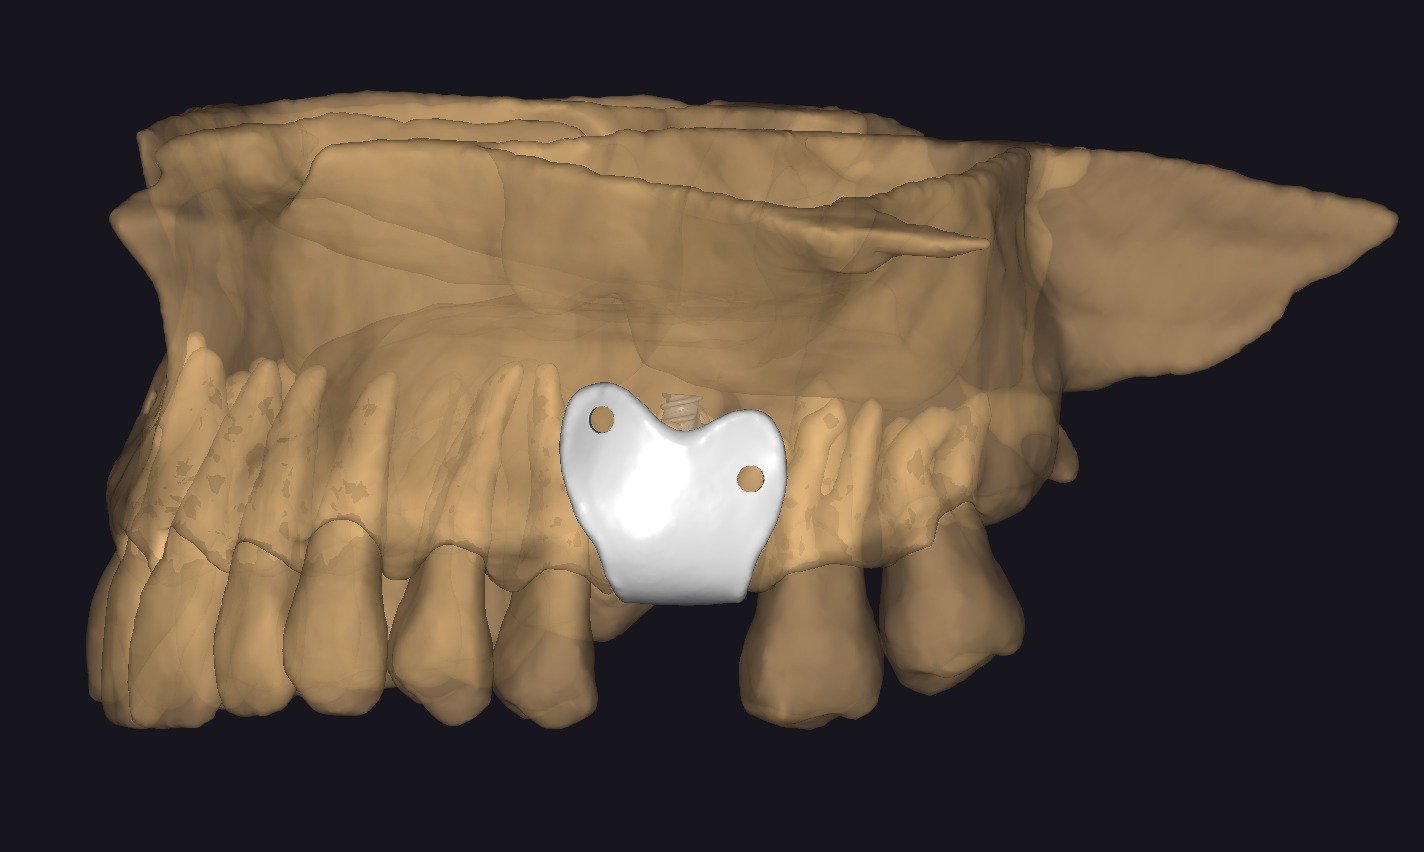

• Concepto de barrera personalizada.

• Principios de diseño biomecánico.

• Espesor, extensión y bordes de la barrera.

• Diseño pasivo y adaptación milimétrica.

• Planificación de tornillos de fijación:

• Número

• Posición

• Angulación

• Relación barrera hueso – tejidos blandos.

• Opciones de fabricación: fresado vs impresión.

• Materiales utilizados.

• Control de calidad del diseño final.

• Ajustes prequirúrgicos.

• Esterilización y preparación para cirugía.